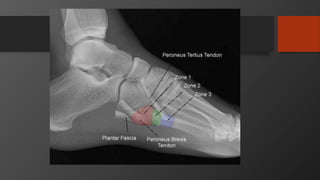

Fifth Metatarsal Fractures

• Common injury

• Divided into 3 zones

• Zone 2 is Jones fracture

• Zone 1 is Pseudojones fracture